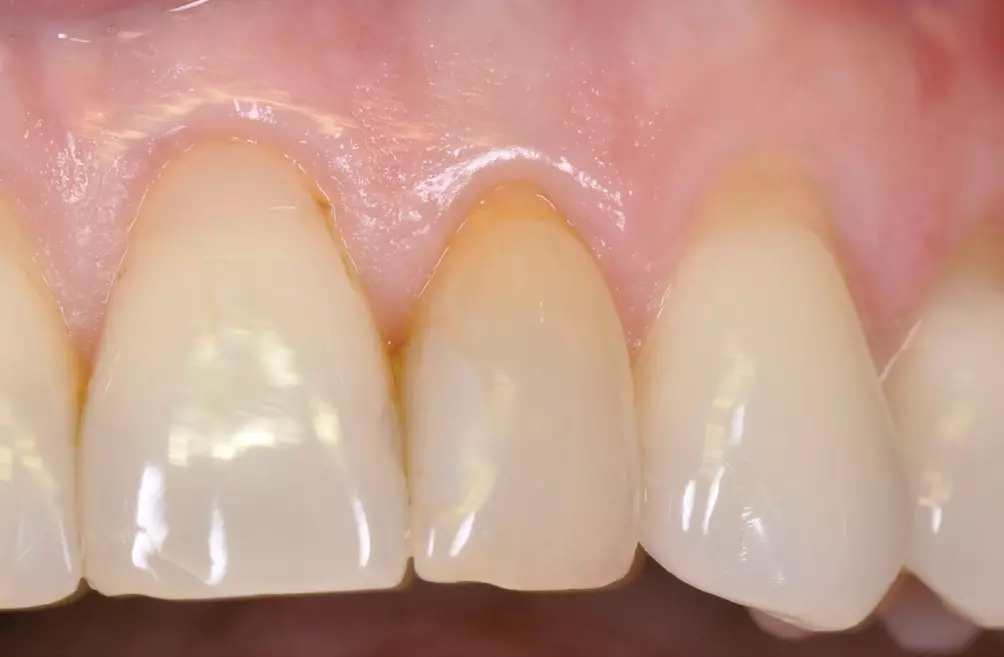

Augenscheinlich sind die ästhetischen Vorteile des Zirkonoxid-Implantatwerkstoffes im Vergleich zum Titan insbesondere in der anterioren ästhetischen Zone bei Patienten mit dünner Gingiva unter 2 mm [47] (Abb. 5–8).

Präklinische und klinische Untersuchungen zu parodontologischen Parametern um „gesunde“ Titan- und Zirkonimplantate zeigen in Bezug auf die Sulcustiefen statistisch signifikante Unterschiede [36,37]. Die Werte erweisen sich sowohl im Tiermodell als auch beim Patienten höher bei den Titanimplantaten im Vergleich zu den Zirkonoxidimplantaten. Erfahrungsgemäß ist eine Sulcus-Sondierung am Zirkonoxidimplantat allerdings aufgrund der dichten fibrösen Gewebestruktur erschwert (Abb. 3).